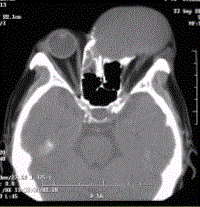

问题 患者男,60岁,头痛,前额部局部隆起。查体:前额隆起处可触及乒乓球样肿块,CT显示如下图。 临床拟诊为

选项 A.额窦黏液囊肿 B.额窦黏膜下囊肿(潴留囊肿) C.额窦急性炎症 D.额窦脓肿 E.脑膜脑膨出 F.额窦骨瘤 G.额窦骨化性纤维瘤

答案 A